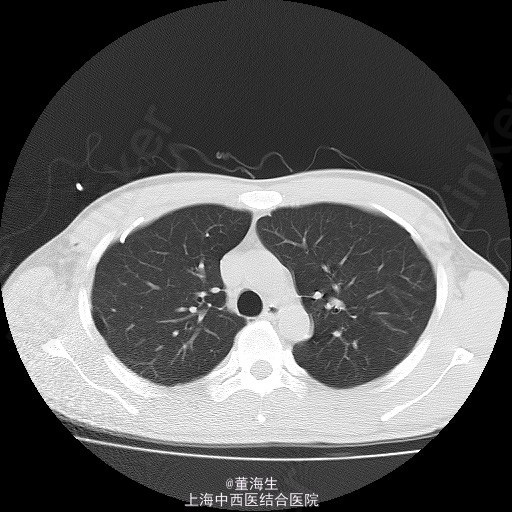

患者,男,39岁。 1.主诉、现病史:患者因为“突发胸闷1日”入院。患者入院当日1:00突觉胸闷,至约16:00来院就诊,辅查胸部CT后如附图1,附图2。既往无类似发作史。 2.查体:患者神清,精神状态良好,生命体征平稳,无气促。右肺听诊呼吸音消失,左侧正常。 3.辅助检查:胸部CT表现如附图1,附图2,血常规提示120g/L,血红蛋白压积正常。 4.诊断:右侧自发性血气胸。 5.处理方案: ①入院后明确诊断,即刻取右侧锁中线第2肋间行胸腔闭式引流。置入8F一次性引流导管一根(该导管头端卷曲,有多个侧孔),导管接水封瓶。静脉给予抗生素及凝血酶,床边心电监护。 ②闭式引流后3小时内引流大量气泡并引流血性液1100ml,即刻复查血常规提示Hgb102g/L。 ③引流3小时后观察引流液不再明显增加,至第二日晨共1400ml血性液,复查血常规仍为102g/L。 ④引流第二日起引流液色逐渐转至浆液性,至入院第6日共引出液体2100ml,负压波动消失,每日引流量少于100ml。予夹闭引流管。 ⑤夹管24小时后复查胸部CT,结果见附图3,附图4。当日予拨除胸腔闭式引流。 6.随访复查:出院后1周,门诊复查胸片及胸水B超,提示无气胸及液胸。 7.分享病例的体会: 实习时老师教导,每小时胸引>200ml血性液,应急诊行剖胸探查。该病例实际治疗时因读片提示胸腔大量积液,保守估计该有1500ml左右,且发病至入院已约15小时,且患者生命体征平稳。故治疗时采取的思路为先放尽积液再计算单位时间内引流量,同时密切观查患者生命体征变化。 此病例没有盲从缺少先决条件的临床条例,免除了患者的手术痛苦。 是否得当请广大同行指正!